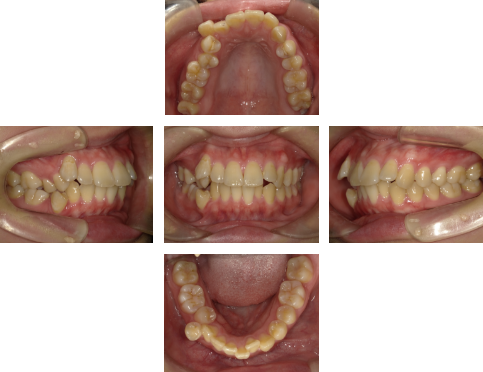

【初診時】

初診時の口腔内写真では、特に上下右側の歯列の乱れが認められました。

また、上下の歯が適切な位置で噛み合っておらず、咬合の不調和が見られます。